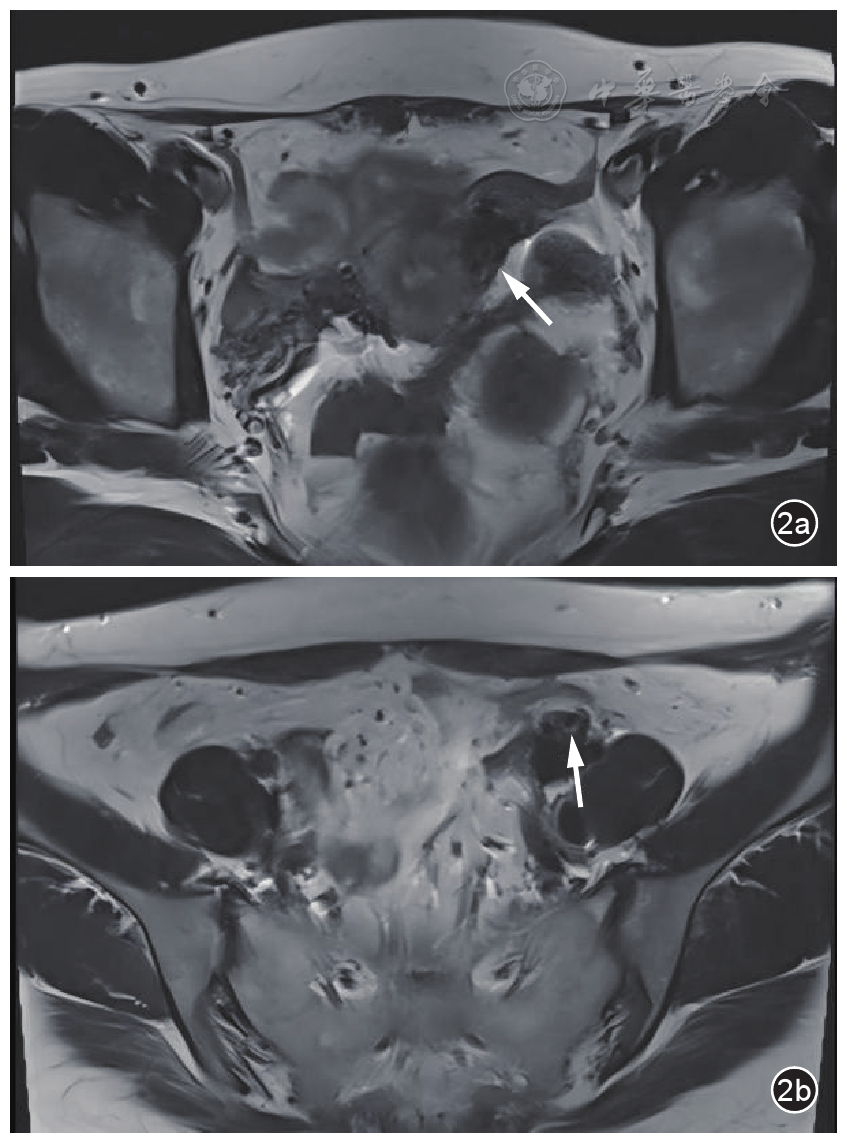

图1 盆腔静脉侵袭性葡萄胎患者化疗前盆腔超声图像。图a,d为经阴道超声纵切面图像显示左侧盆腔静脉内多发囊泡状无回声及条索状中等回声(长箭头),左侧壁上段临近浆膜层处中高回声(短箭头)与宫旁扩张静脉内异常回声相连;图b,e为扩张宫旁静脉内见数个囊泡状无回声,彩色多普勒血流成像(CDFI)显示其内血流信号充盈缺损;图c,f为扩张髂静脉内见囊泡状无回声,CDFI显示其内血流信号充盈缺损

入院妇科查体左附件区呈增厚感,无压痛,右附件区未见异常。经阴道超声检查显示子宫宫腔内可见支架回声,内膜菲薄,左侧壁上段临近浆膜层处肌层回声不均,局部可见团块状中高回声,大小1.4 cm×1.3 cm;左侧宫旁静脉及髂静脉显著扩张,最宽处达到1.4 cm,内部可见多个薄壁囊泡状无回声及条索状的中等回声结构,其中较大的无回声直径约为0.9 cm。动态观察显示子宫左侧壁上段临近浆膜层处中高回声与宫旁扩张静脉内异常回声相连。双侧附件区未见明确囊实性包块。彩色多普勒血流成像(color Doppler flow imaging,CDFI)显示宫旁扩张静脉及髂静脉的囊泡状无回声内未见血流信号,周边残余管腔血流充盈尚可(图1)。超声检查提示子宫肌层及左侧盆腔静脉内异常回声,结合临床考虑侵袭性葡萄胎可能。盆腔动态增强MRI显示子宫左侧壁上段可见小囊状长T2信号,邻近伴多发迂曲略粗血管流空信号;左侧附件区可见不规则小片状等T2信号及多发小囊状长T1长T2信号,强化不均,邻近宫旁静脉迂曲增粗呈蚓状,范围约4.4 cm×1.7 cm,提示左侧附件区及子宫左侧壁上段见多发异常信号及血管流空影,妊娠滋养细胞肿瘤不除外(图2)。患者胸部CT、心脏超声、心电图未见明显异常。